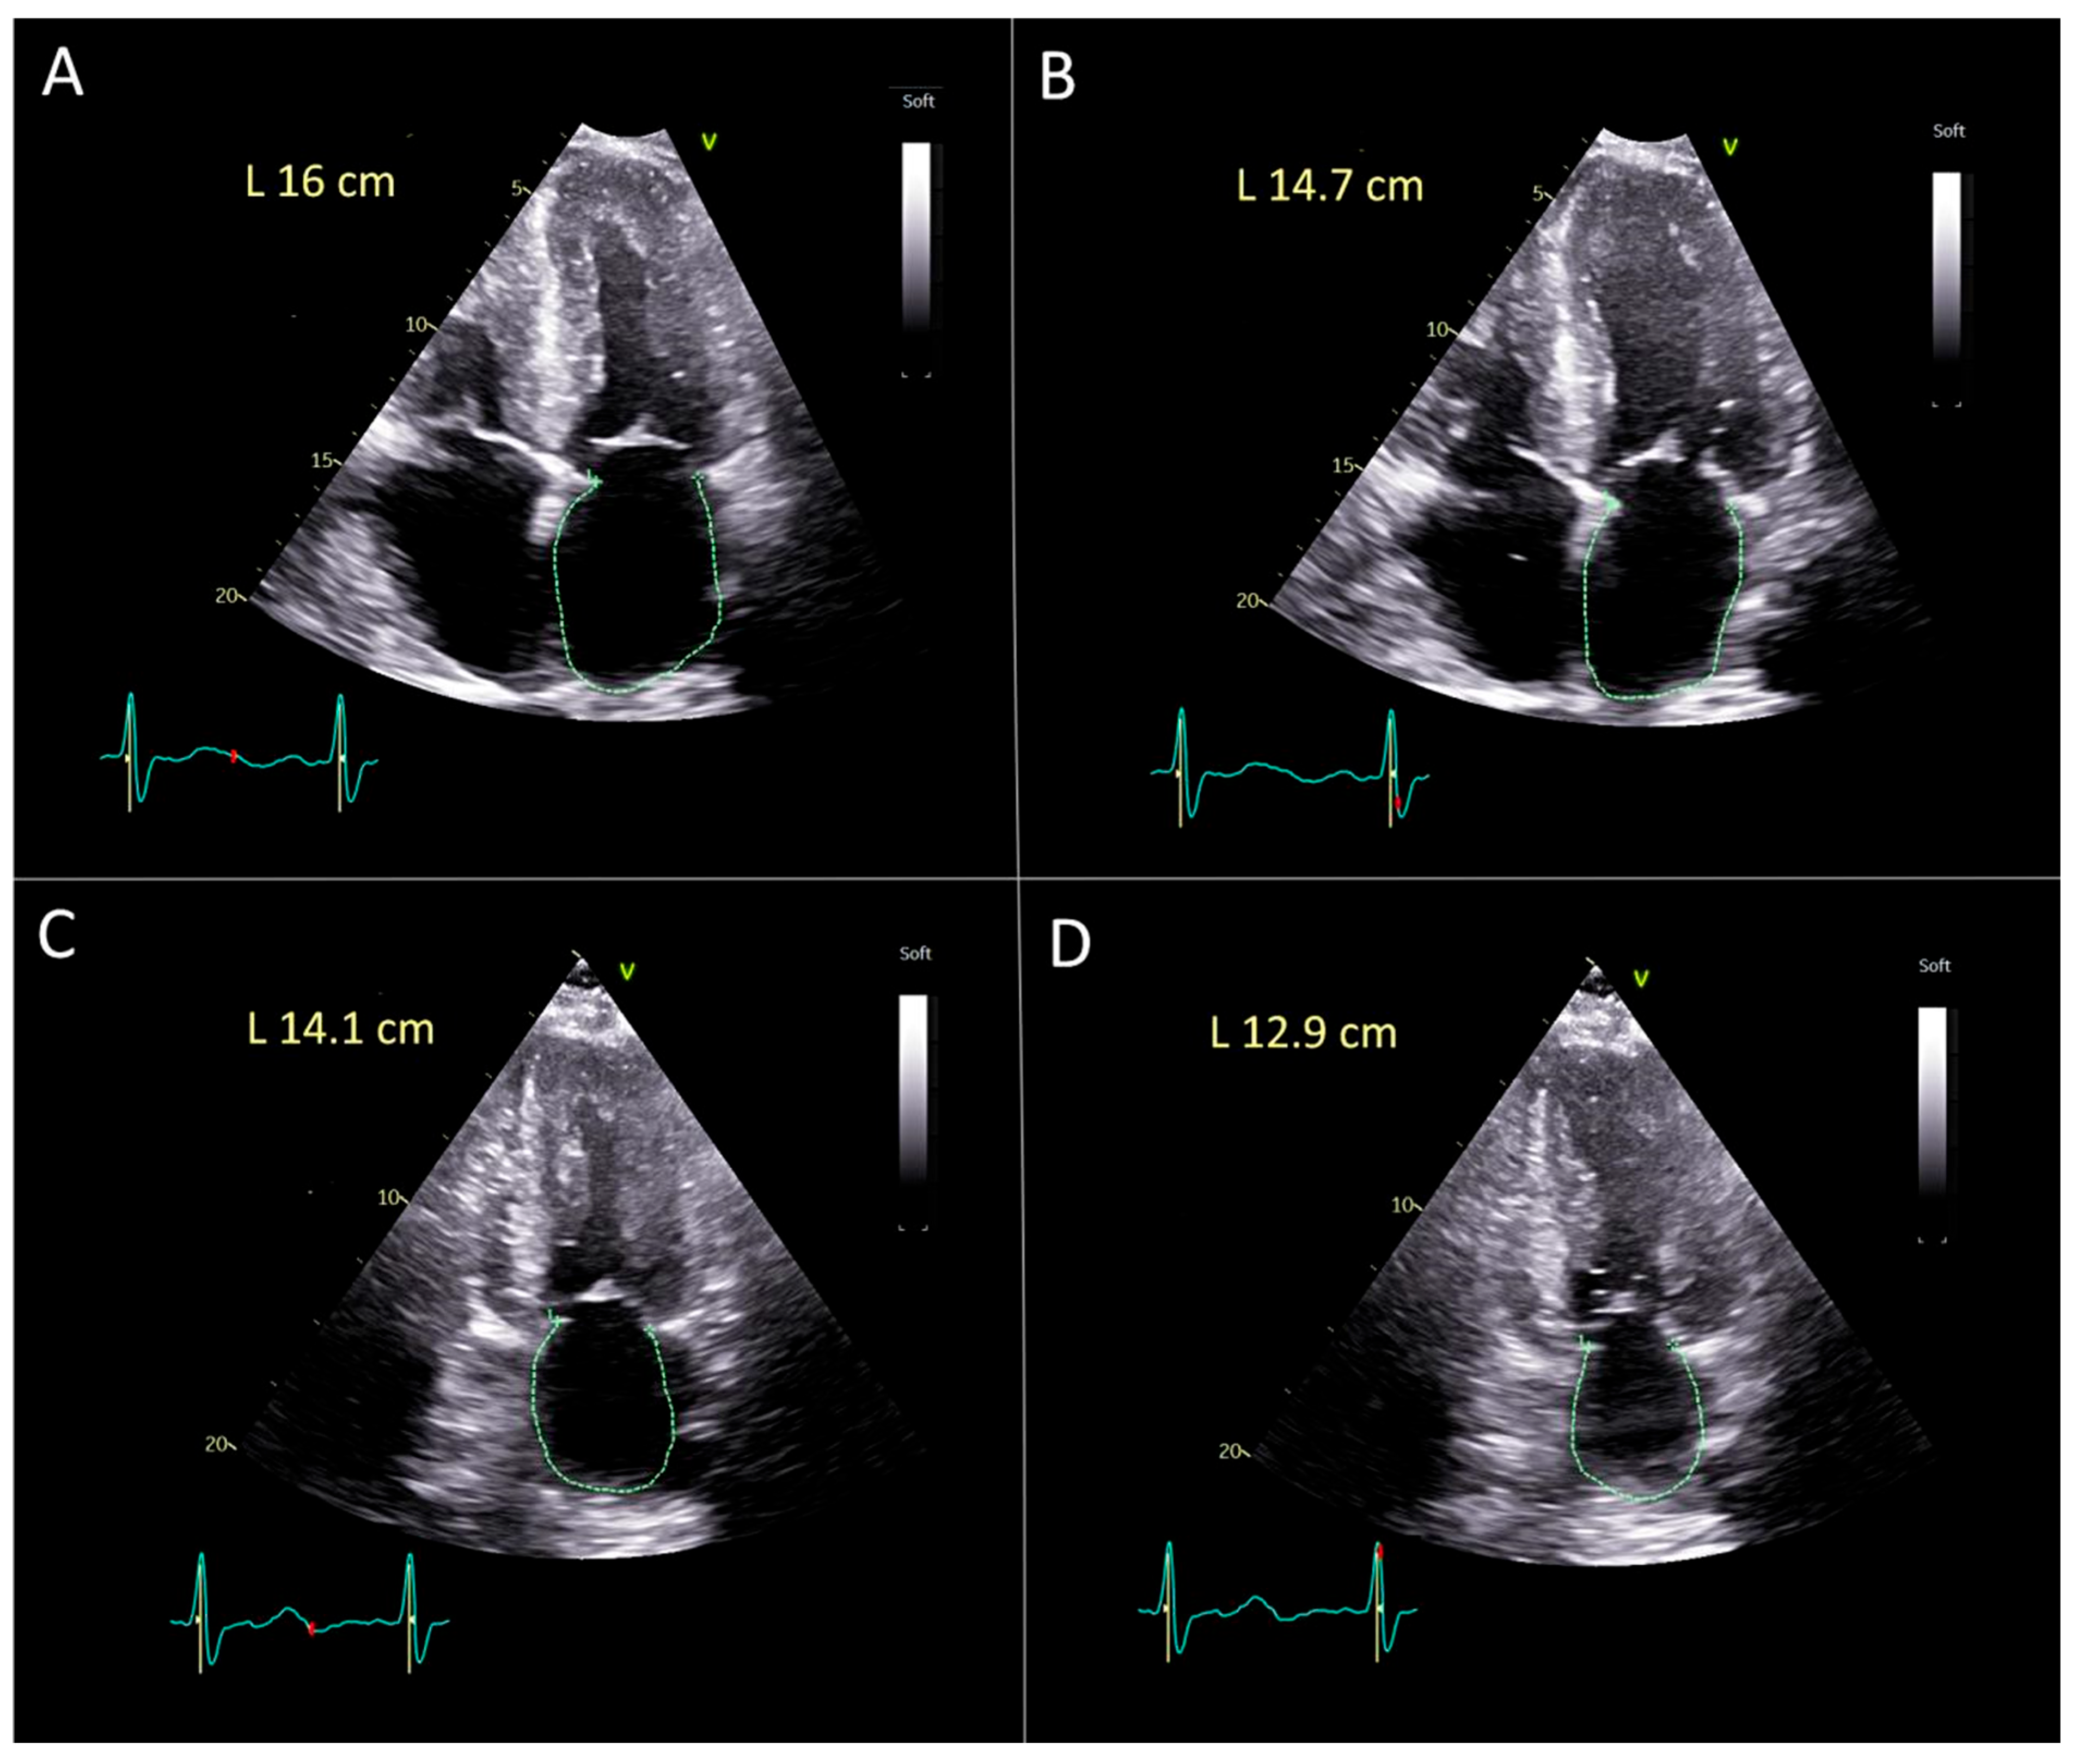

Validation of Manual Method for the Left Atrial Strain Calculation